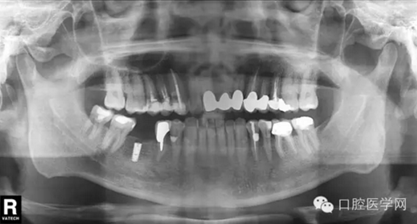

第三種是德國(guó)Ankylos種植體

第四種,韓國(guó)奧齒泰種植體

第五種,瑞士士卓曼種植體(也稱ITI種植體)